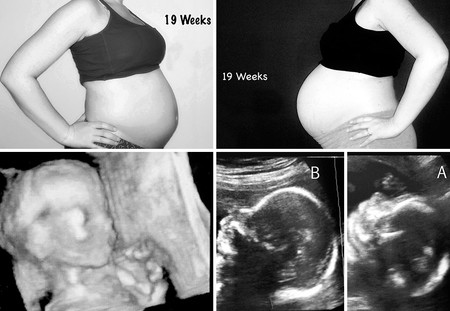

Diecinueve semanas de embarazo

Gemelos3